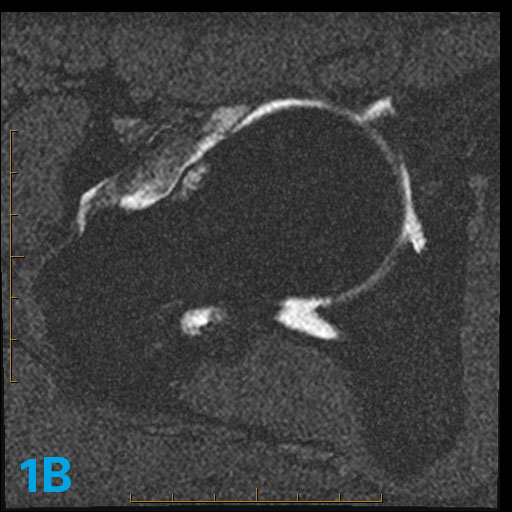

The three axial oblique images in this 43-year-old with hip pain demonstrate an abnormality. What are the associated potential imaging findings that might accompany this abnormality?

The lack of tapering of the femur head to the neck is known as asphericity. This lack of tapering is associated with a bump in the anterior aspect of the femoral head neck junction. The bump is also associated with a friction-related pseudocyst ("herniation pit") that occurs when the hip is in flexion and especially in flexion-internal rotation as this area rubs across the acetabulum. Sometimes the friction produces edema but not an actual cyst.

Clinically, such patients often experience pain in hip flexion worse in internal more than external rotation. This case illustrates an axial oblique head neck junction shape of Cam or Type 1 hip impingement syndrome. For more case review, check out MRI Online.